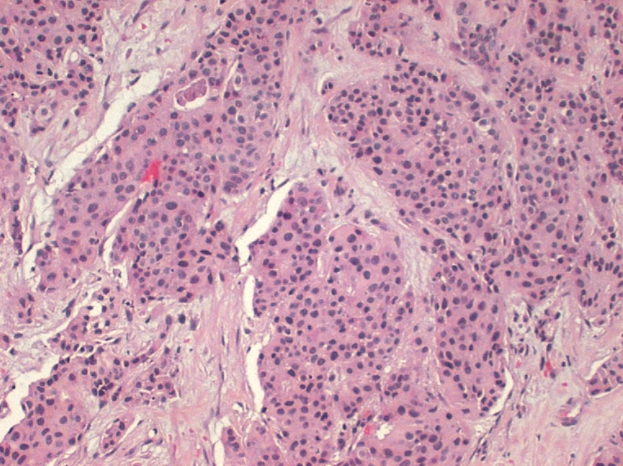

What type of breast cancer is shown?

Invasive ductal carcinoma